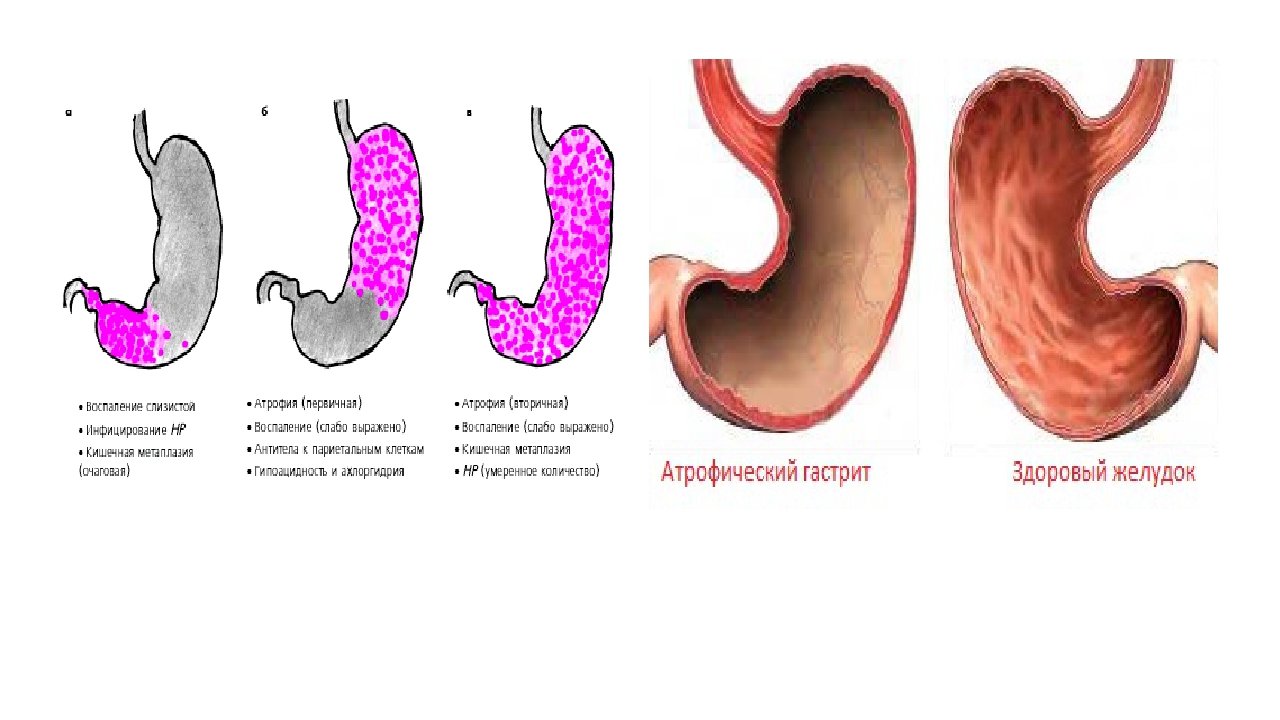

Информация и фотографии о хроническом гастрите и дуодените